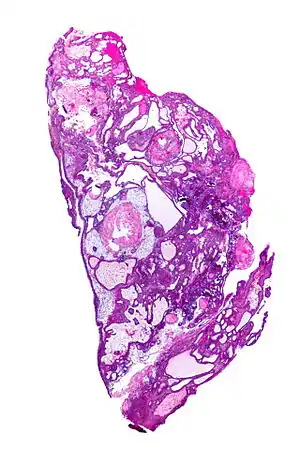

Very low magnification micrograph of an adamantinomatous craniopharyngioma. HPS stain. | |

On macroscopic examination, craniopharyngiomas are cystic or partially cystic with solid areas. On light microscopy, the cysts are seen to be lined by stratified squamous epithelium. Keratin pearls may also be seen. The cysts are usually filled with a yellow, viscous fluid rich in cholesterol crystals. Of a long list of possible symptoms, the most common presentations include headaches, growth failure, and bitemporal hemianopsia.

- Micrograph showing the characteristic features of an adamantinomatous craniopharyngioma - cystic spaces, calcifications, and "wet" keratin, HPS stain